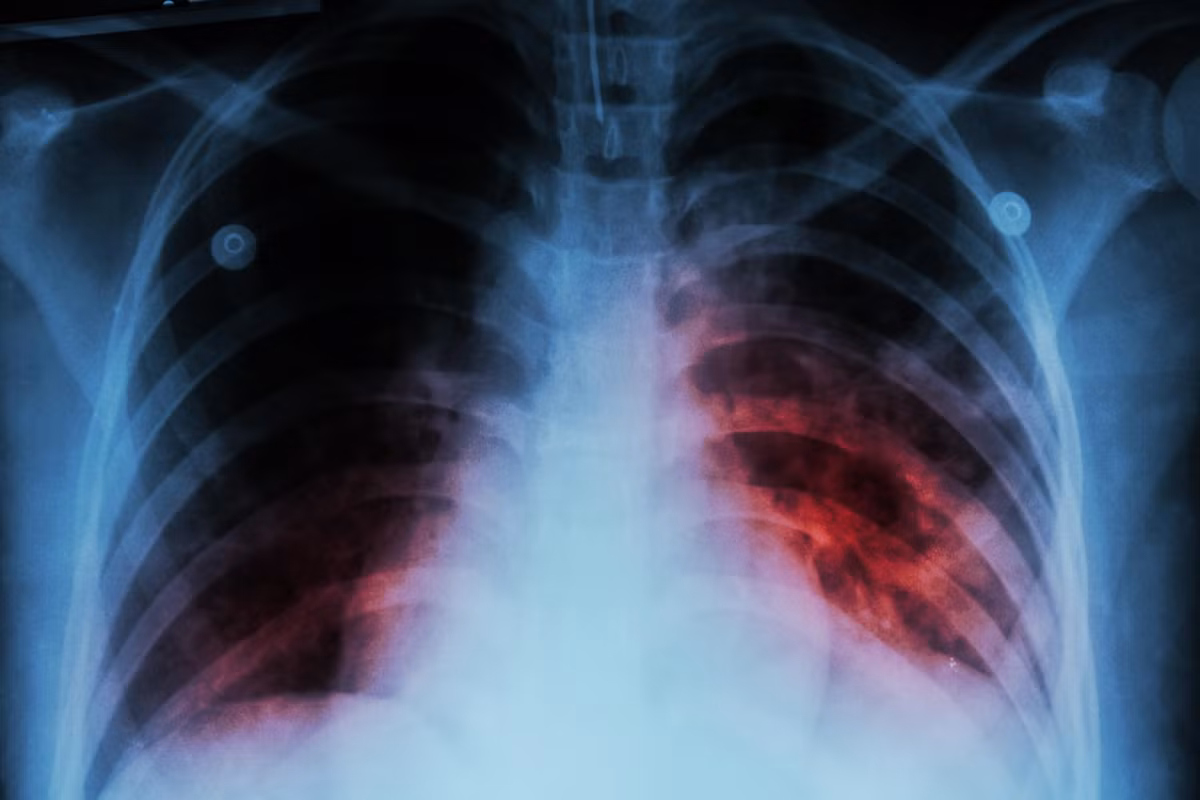

Benh truyen nhiem gay tu vong nhieu nhat the gioi-Hinh-2

Lao là bệnh do vi khuẩn gây ra, ảnh hưởng chủ yếu đến phổi. Ảnh: iStock.